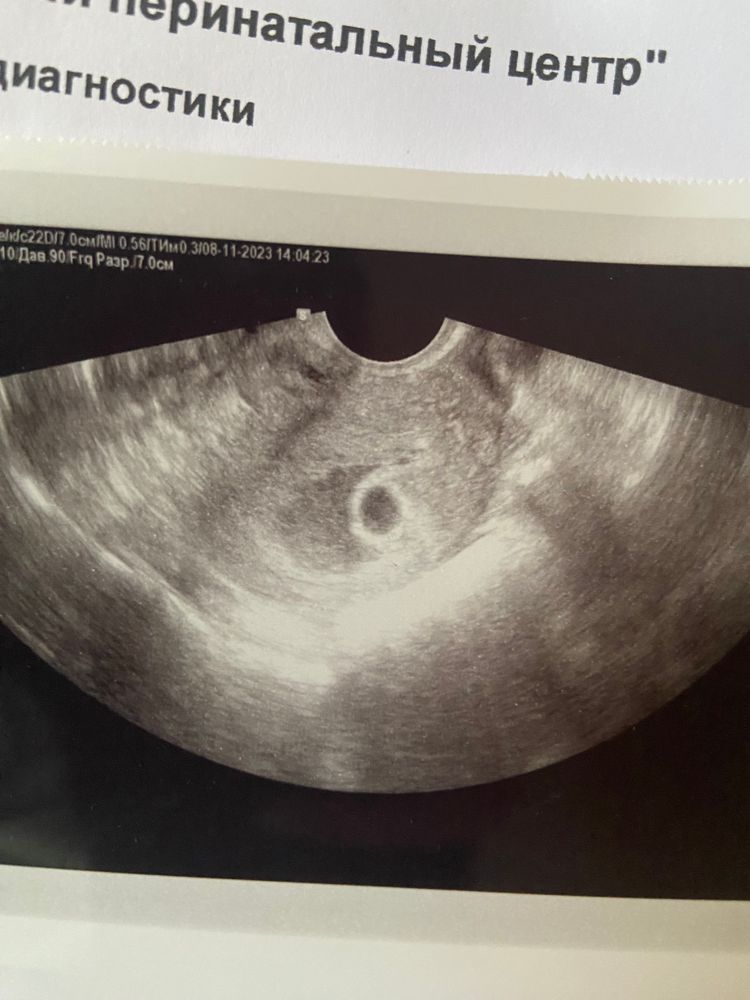

Эмбрион, желточный мешочек?

Девочки сходила на узи, написали желточный мешочек и эмбрион не визуализируются , сейчас присмотрелась и что то вижу ?! Оно или это блики узи 🤷♀️

Возможно просто кратинка такая на узи, т. К. Обычно плодное яйцо внутри гораздо темнее. Может быть очертания будущего жм. Смущает такая область темноватая возле пя, полумесяцем. У меня так гематома выглядела.

у меня такая картинка была, но увы-анэмбриония.... У вас какой срок? Может еще рано?

Есть какая-то тень небольшая. Какого размера у вас плодное яйцо? Может еще рано просто)